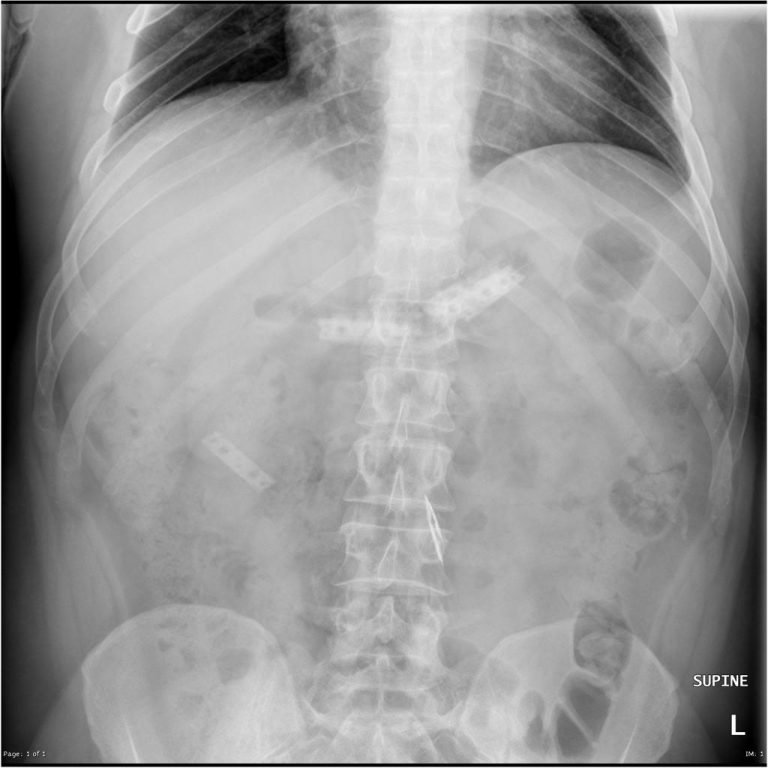

From buyxraysonline.com

SWALLOWED RAZOR BLADES What Happens If You Eat Razor Blades A sore throat can fall anywhere between slight discomfort and a sensation of swallowing razor blades. A 16 year old boy with a long history of self harm was admitted for the third time. If you’ve ever felt like you were swallowing razor blades, you’re not alone. The first patient that we managed ingested an entire razor blade wrapped in. What Happens If You Eat Razor Blades.